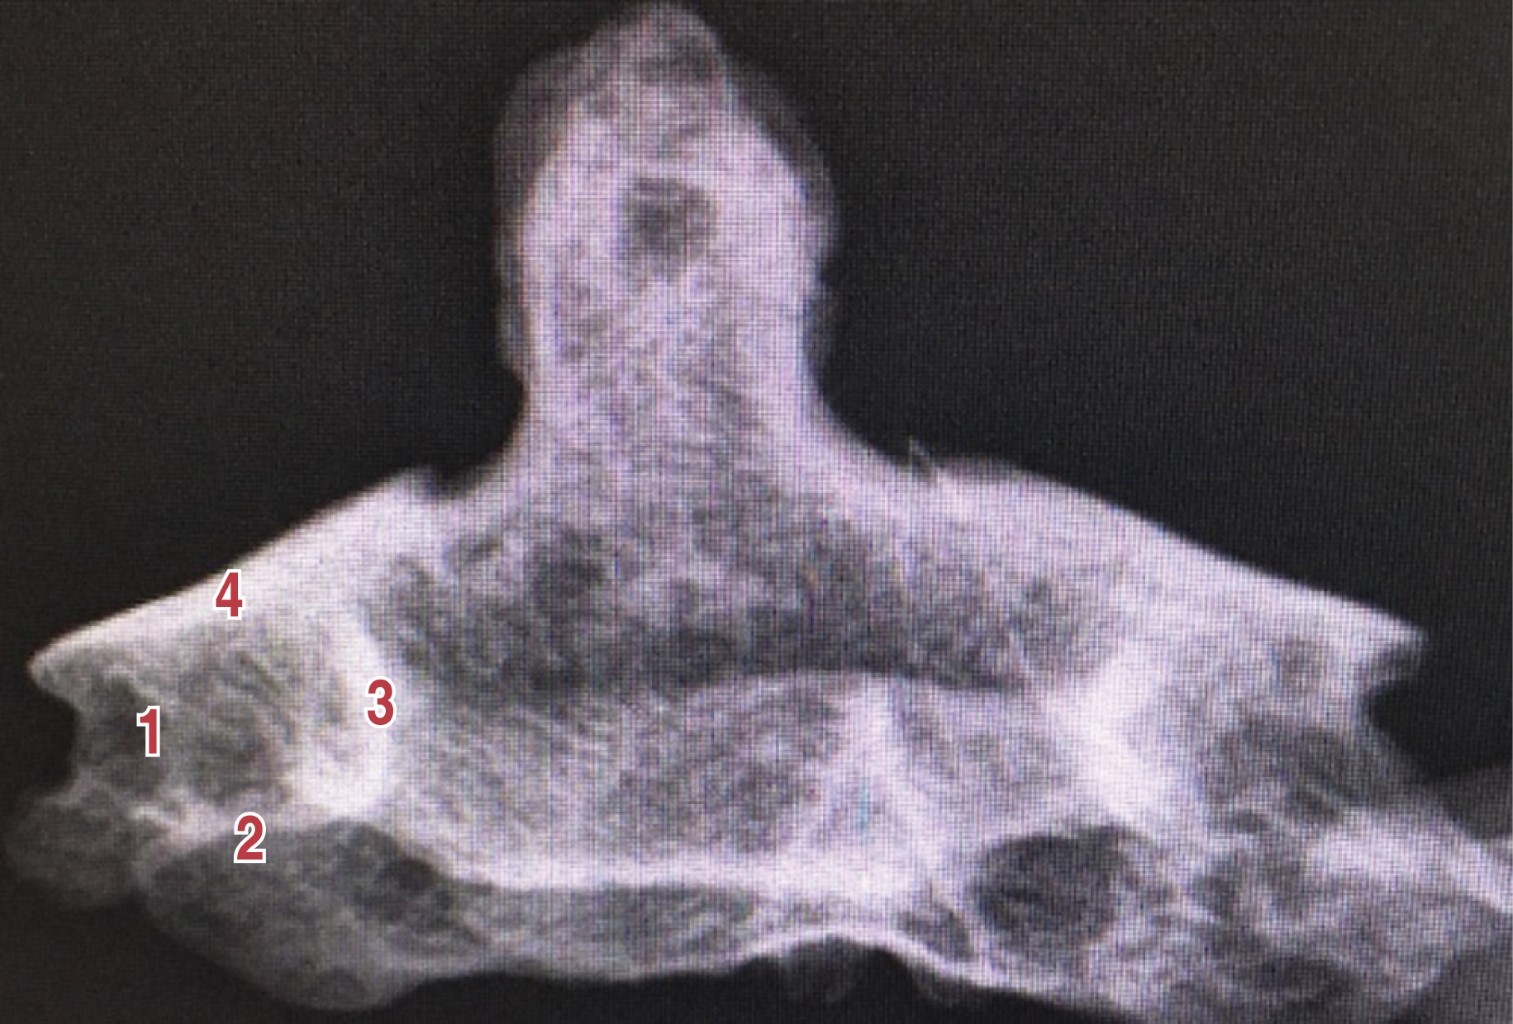

Posicionamos al paciente en decúbito prono, manteniendo la posición de la cabeza con la dona quirúrgica. Mantenemos la boca abierta colocando gasas para mantener los dientes fuera de la proyección anteroposterior de C2. El tubo endotraqueal se pegó a la comisura labial y se deprimió el mismo contra la lengua para así evitar que se proyecte el alma de acero sobre la zona de entrada al pedículo. Se realizó abordaje cervical posterior convencional y la exposición de los elementos vertebrales posteriores de C2, liberando adecuadamente las carillas articulares de la unión atlantoaxial y C2-C3. Bajo la guía fluoroscópica en proyección anteroposterior localizamos la zona de entrada al pedículo (Figura 1). Esta zona de entrada se encuentra formado por dos paredes, un piso y un techo que corresponden a las siguientes estructuras anatómicas: la pared lateral se encuentra formada por la pared medial del foramen transverso de la arteria vertebral, el piso está formado por la carilla articular inferior de C2, la pared medial está formada por la lámina de C2 y el techo está formado por la carilla articular superior de C2.

Figura 1